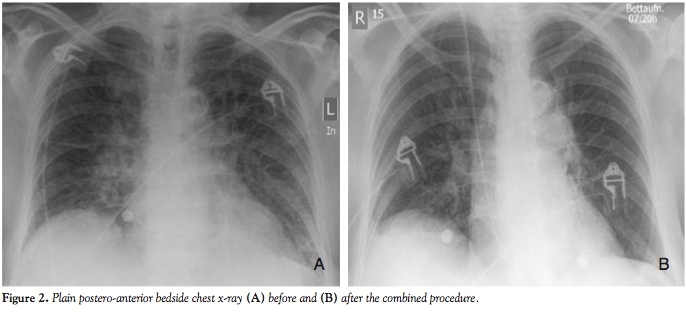

Case Report. An 84-year-old, diabetic, hypertensive and obese woman presented with a non-ST segment elevation myocardial infarction and impending pulmonary edema. She gave history of recently worsening dyspnea on minimal exertion (New York Heart Association class III) together with effort angina on mild exertion with marked limitation of her ordinary activity (Canadian Cardiovascular Society class III) over the previous 6 months. Cardiac examination revealed the presence of a harsh ejection systolic murmur over the cardiac base radiating to the neck (grade IV), and bilateral fine rales were audible over the basal and mid fields of her lungs, denoting pulmonary congestion. Her electrocardiogram showed ST-segment depression and T-wave inversion in the lateral chest leads (V3–V6) together with leads I, aVL and lead II (Figure 1), and her chest x-ray confirmed the presence of severe pulmonary congestion (Figure 2A). Troponin T, total creatine kinase (CK) and CK-MB were elevated. An echocardiography done a few months before admission showed evidence of severe aortic stenosis, yet the patient

The patient was kept in the intensive care unit for 3 more days and then transferred to the department for further management and rehabilitation. She reported rapid relief of her symptoms with marked improvement in her functional capacity (Figure 2B). Dual antiplatelet therapy (aspirin 100 mg/day and clopidogrel 75 mg/day) was advised for 6 months, and aspirin was prescribed lifelong. Thirty-day follow-up echocardiography revealed a well functioning